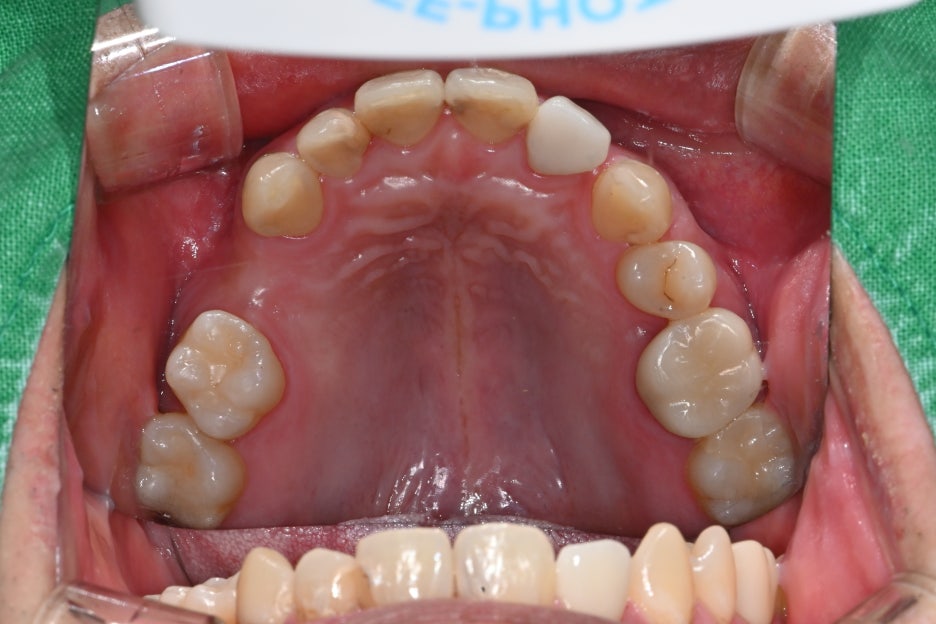

처음 내원 당시 사진

송파구 임플란트